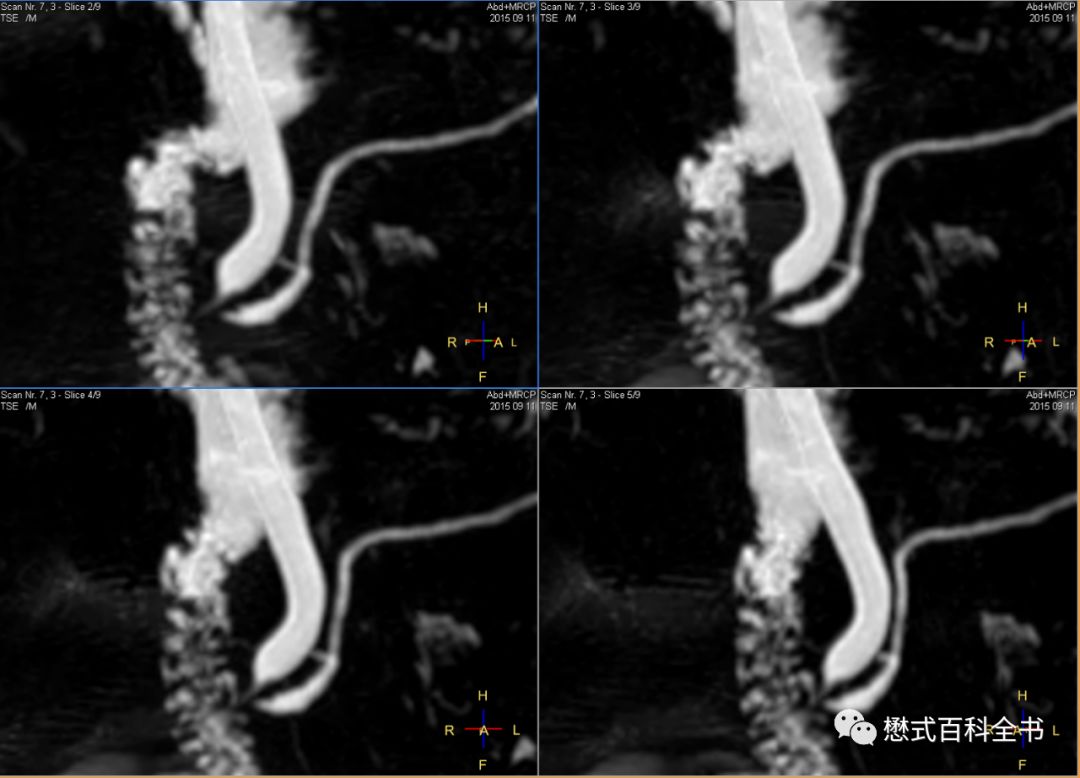

图21:3D MRCP扫描

如图,3D MRCP扫描,容积采集后,然后做MIP(最大信号强度投影重建)。

3D MRCP优点是:信噪比高,可以出薄层图像,而且可以通过图像后处理MIP形成胆管树形结构图,这种图临床医生非常喜欢看,对胆管系统整体结构显示清晰。

但是,3D MRCP也有致命的缺点,如图,如果没有经验的影像医生或者临床医生只看重建的MIP图,而不看原始的薄层图像,则容易出现假阴性(由于最大信号强度投影的图像后处理算法关系,有可能把本来的充盈缺损,显示结石的给遮掩了)。本来有结石的,结果做了MIP后,无法显示充盈缺损了。另外,3D MRCP序列扫描时间也长。

图22:2D MRCP扫描

如图,2D单激发MRCP扫描。一次激发采集一层或者多层。

2D MRCP优点是:扫描速度快。一次激发采集1层或者多层,直接出图像,能够很好的显示结石的充盈缺损。

缺点是:信噪比比3D的低,一次扫描出1~几层,单层层厚厚,有部分容积效应。

所以,理论上为了保证好的诊断效果,我们推荐3D MRCP和2D ssh MRCP都要扫描。当然,3D MRCP扫描完,一定要看原始薄层图像,有经验的诊断医生不可能只看MIP图去诊断。

图23:3D MRCP,原始的薄层图像(原始图是非常重要的)

3D MRCP扫描完,一般会进行一些图像后处理,比如MIP,当然也有医院为了图像美观进行裁剪,把多余不要的部分修剪掉。当然,直接MIP生成图像也是可以的。临床医生比较喜欢看重建的MIP图,因为它的胆管树形结构显示清楚。但是,作为放射科医生,一定要注意,在诊断的时候,必须看原始的薄层图。